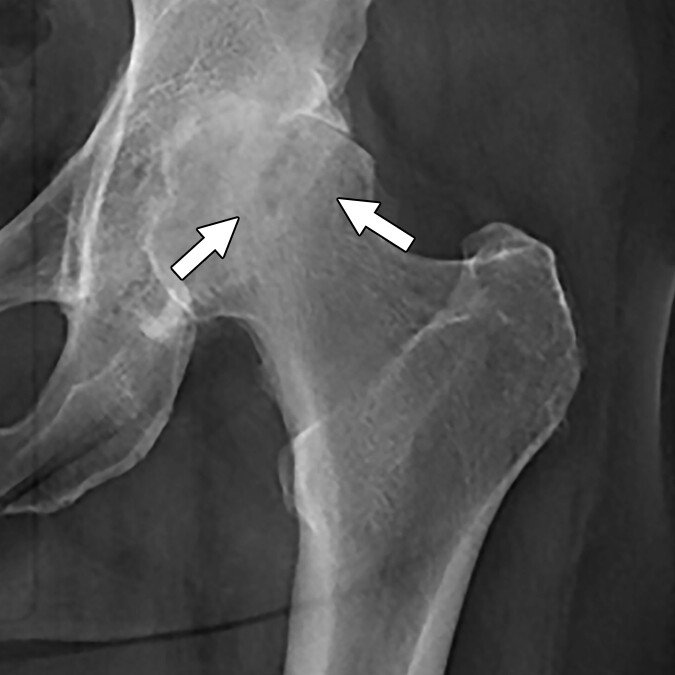

Avascular Necrosis (AVN)

A loss of blood supply to the hip bone leading to joint collapse and chronic pain

Avascular necrosis (AVN), also known as osteonecrosis, is a serious condition that occurs when the blood supply to a section of bone is disrupted. In the hip, this typically affects the femoral head, the ball-shaped part of the thigh bone that fits into the hip socket. Without adequate blood flow, the bone tissue begins to die, which can cause the femoral head to weaken, flatten, and eventually collapse.

What is avascular necrosis (AVN) of the hip?

Avascular necrosis (AVN), also known as osteonecrosis, is a condition that occurs when the blood supply to the femoral head (the ball of the hip joint) becomes disrupted. Without adequate blood flow, the bone tissue begins to die, leading to the collapse of the femoral head, joint deterioration, and eventually, arthritis. The hip is the most commonly affected joint in AVN, although other joints such as the shoulder or knee may also be involved.

How is AVN diagnosed?

- X-rays: Useful for identifying late-stage AVN or femoral head collapse